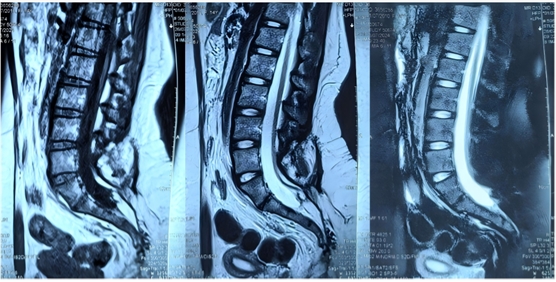

患者,女,15岁,出生后即发现腰骶部偏左侧包块,两侧臀部不对称,11个月时发现包块增大,考虑为脊髓拴系、脊髓脂肪瘤。2岁左右出现排尿费力、尿失禁(伴尿床),遂于某儿童医院接受脊髓拴系松解术。术后二便功能障碍进行性加重,且出现下肢畸形,1年前复查发现脊髓拴系术后复发(图一),遂于我科行二次松解手术。术后病情稳定(图二),未再有加重趋势,仍遗留大小便失禁,表现为小便漏尿,伴有排尿费力,且小便都是滴出,自己不能感知。大便干燥便秘,至少三四天一次大便,大便费力,稀的时候失禁。

图1为1年前脊髓拴系松解术前磁共振检查片子

图2为此次手术前复查腰骶椎MR检查,提示脊髓拴系松解满意